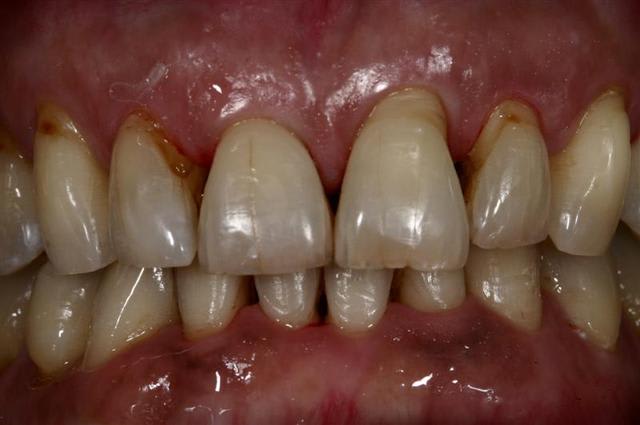

Envie d'améliorer le sourire... petit traitement d'alignement avec une technique simple et efficace à la portée de tous la preuve...

Pourtant j'en ai fait des contentions...(Attelle or avec pins, cavalier, Ribbond, etc etc...)

Quelques photos jointes pour vous'assurer que je ne bluffe pas ;)